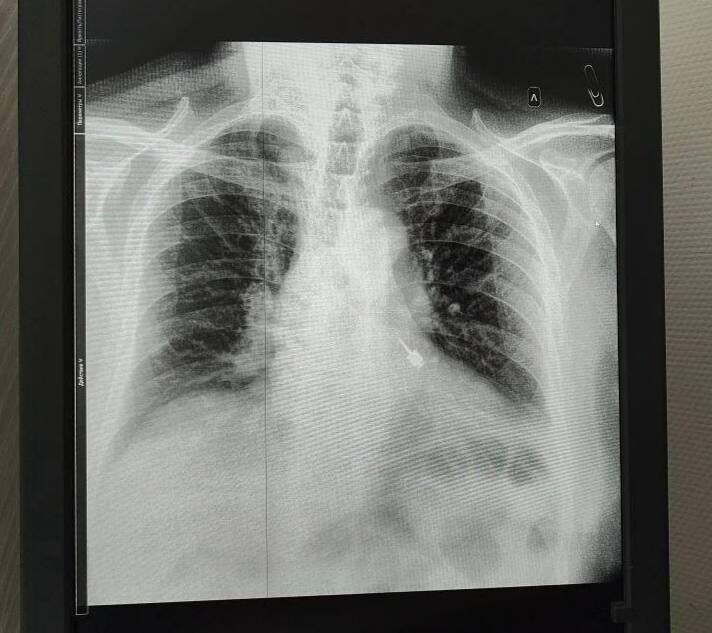

🀯 БтоматологичСский Π±ΡƒΡ€ ΠΏΠΎΠΏΠ°Π» Π² Π±Ρ€ΠΎΠ½Ρ… ΠΏΠ°Ρ†ΠΈΠ΅Π½Ρ‚Π° Π²ΠΎ врСмя лСчСния Π·ΡƒΠ±ΠΎΠ²

Π˜Π½Ρ†ΠΈΠ΄Π΅Π½Ρ‚ ΠΏΡ€ΠΎΠΈΠ·ΠΎΡˆΡ‘Π» Π² частной ΠΊΠ»ΠΈΠ½ΠΈΠΊΠ΅ Π² ПодмосковьС: Π²ΠΎ врСмя ΠΏΡ€ΠΈΡ‘ΠΌΠ° ΠΌΡƒΠΆΡ‡ΠΈΠ½Π° ΠΏΡ€ΠΎΠ³Π»ΠΎΡ‚ΠΈΠ» стоматологичСский инструмСнт, ΠΈ Ρ‚ΠΎΡ‚ оказался Π² Π»Π΅Π²ΠΎΠΌ Π±Ρ€ΠΎΠ½Ρ…Π΅.

ΠŸΠ°Ρ†ΠΈΠ΅Π½Ρ‚Π° срочно доставили Π² Π±ΠΎΠ»ΡŒΠ½ΠΈΡ†Ρƒ, Π³Π΄Π΅ Π²Ρ€Π°Ρ‡ΠΈ ΠΏΡ€ΠΎΠ²Π΅Π»ΠΈ ΠΎΠΏΠ΅Ρ€Π°Ρ†ΠΈΡŽ. МСдики ΠΎΡ‚ΠΌΠ΅Ρ‡Π°ΡŽΡ‚, Ρ‡Ρ‚ΠΎ ΠΏΡ€ΠΎΠΌΠ΅Π΄Π»Π΅Π½ΠΈΠ΅ ΠΌΠΎΠ³Π»ΠΎ Π·Π°ΠΊΠΎΠ½Ρ‡ΠΈΡ‚ΡŒΡΡ Π»Π΅Ρ‚Π°Π»ΡŒΠ½Ρ‹ΠΌ исходом. Бпустя нСдСлю ΠΌΡƒΠΆΡ‡ΠΈΠ½Ρƒ выписали, сСйчас ΠΎΠ½ чувствуСт сСбя Ρ…ΠΎΡ€ΠΎΡˆΠΎ.